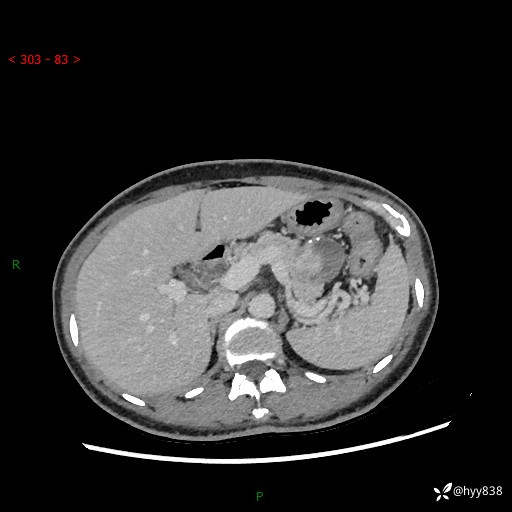

增强动脉期+静脉期

img